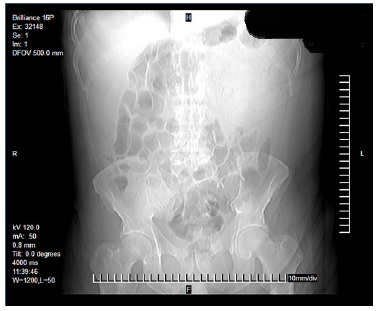

Laboratorios a su ingreso: hemoglobina 9,3 g/dL, hematocrito 29,6 %, plaquetas 574 x 109/L y albumina 1,6 g/dL, resto dentro de parámetros normales. Se realizó una tomografía abdominal que reportó un tumor dependiente del colon transverso con invasión a pared abdominal y formación de absceso (Figura 1, 2 y 3). Con el paciente en estado séptico, se decide el drenaje y la exploración quirúrgica previa estabilización.

La utilidad de la colonoscopia y la biopsia por este medio, han sido las herramientas de tamizaje y diagnóstico temprano [13-15], sin embargo, esta herramienta tiene sus limitaciones al estar confinada a la luz intestinal, así como un riesgo de error en la toma de biopsia en caso de un tumor heterogéneo. En los casos de absceso de pared abdominal, independientemente de su origen, la tomografía juega un papel crucial en el diagnóstico [10,16].